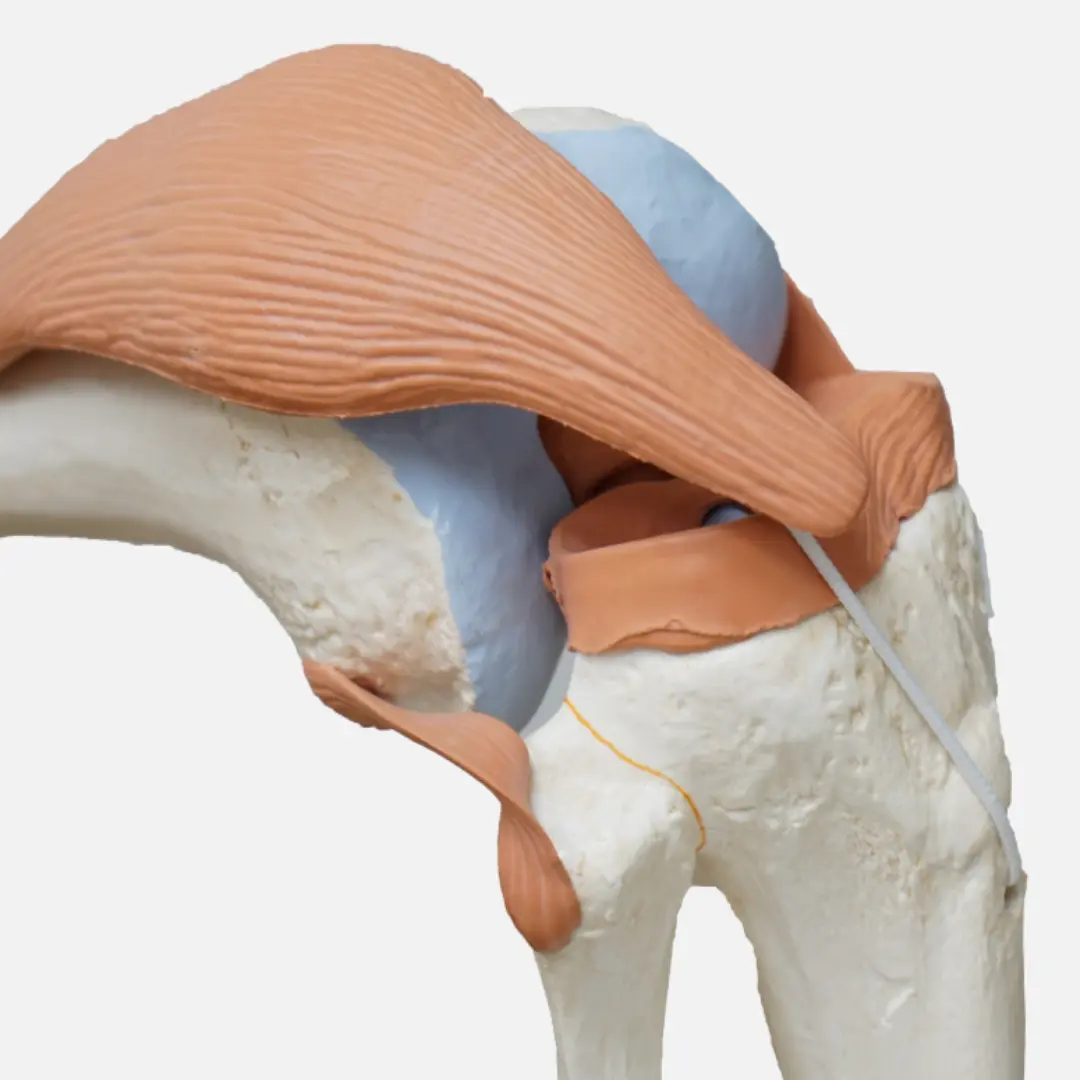

- 자가면역 반응: 면역 체계가 관절을 감싸는 활막(synovial membrane)을 공격하여 염증을 유발하는 것이 근본적인 원인이에요. 활막은 관절액을 생성하여 관절을 윤활하는 역할을 하는데, 여기에 염증이 생기면 관절이 붓고 통증을 유발한답니다.

- 히알루론산 주사 (연골 주사): 관절액 성분인 히알루론산을 관절 내에 주입하여 관절의 윤활 작용을 돕고 연골을 보호하며 통증을 완화하는 데 사용돼요. 주로 퇴행성 관절염 초기~중기에 적용된답니다.